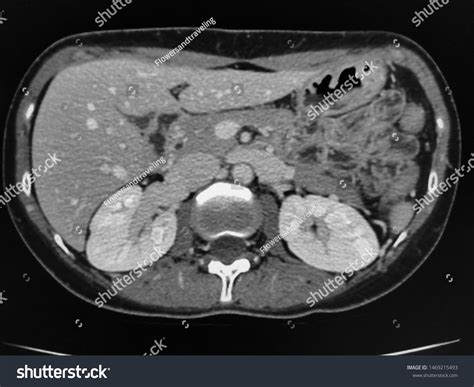

• Imaging Tests: Such as ultrasound, CT scan, and MRI to visualize the organs.